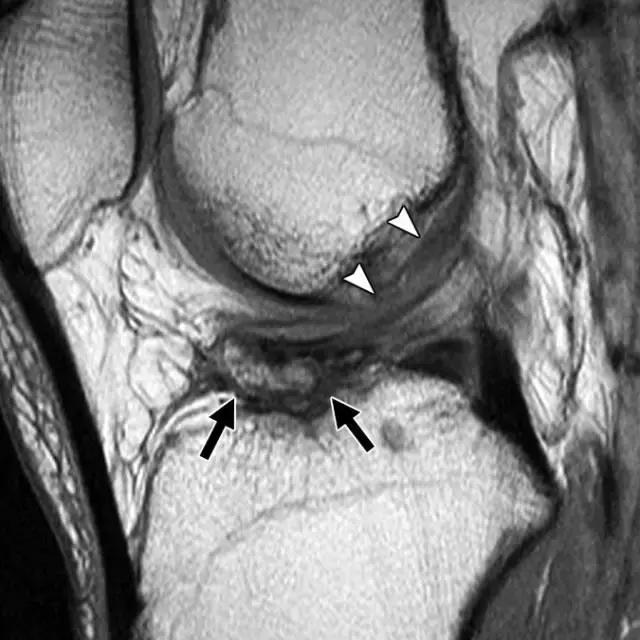

弓形骨折是近端腓骨的小撕裂性骨折。 在前后X光照片上最佳可视化,弓形标志是指通常位于腓骨头附近的腓骨腓骨片段(图10A)。 断裂与弓形复合体的一种或多种组分的撕裂有关,其可以包括以下结构:股二头肌;侧副韧带;腘肌肉和腱; 腘腓骨和腘半月板韧带;和斜腘,弓形和腓肠豆腓侧韧带。 骨折不仅表现为外侧膝盖的临床重要的软组织损伤,而且通常与其他损伤有关。 在一项研究中,72%的弓形骨折患者也有ACL损伤,67%的患者出现PCL撕裂(图10B)。

图10A -26岁的女子与弓形标志。膝关节前后X线照片显示位移水平方向的腓骨头骨折(箭头)和外侧关节隔室的加宽。

图10B,冠状脂肪抑制的T2加权MR图像显示撕脱骨折(黑色箭头)和广泛的软组织水肿和外侧副韧带(箭头)和腘腱(白色箭头)的撕裂。

后外侧角损伤的临床诊断可能是具有挑战性的,因为身体检查中的发现通常是轻微的。 因此,成像在这些患者的治疗中起关键作用,因为在ACL或PCL重建时未能识别后外侧角部损伤,可能导致早期移植失败。